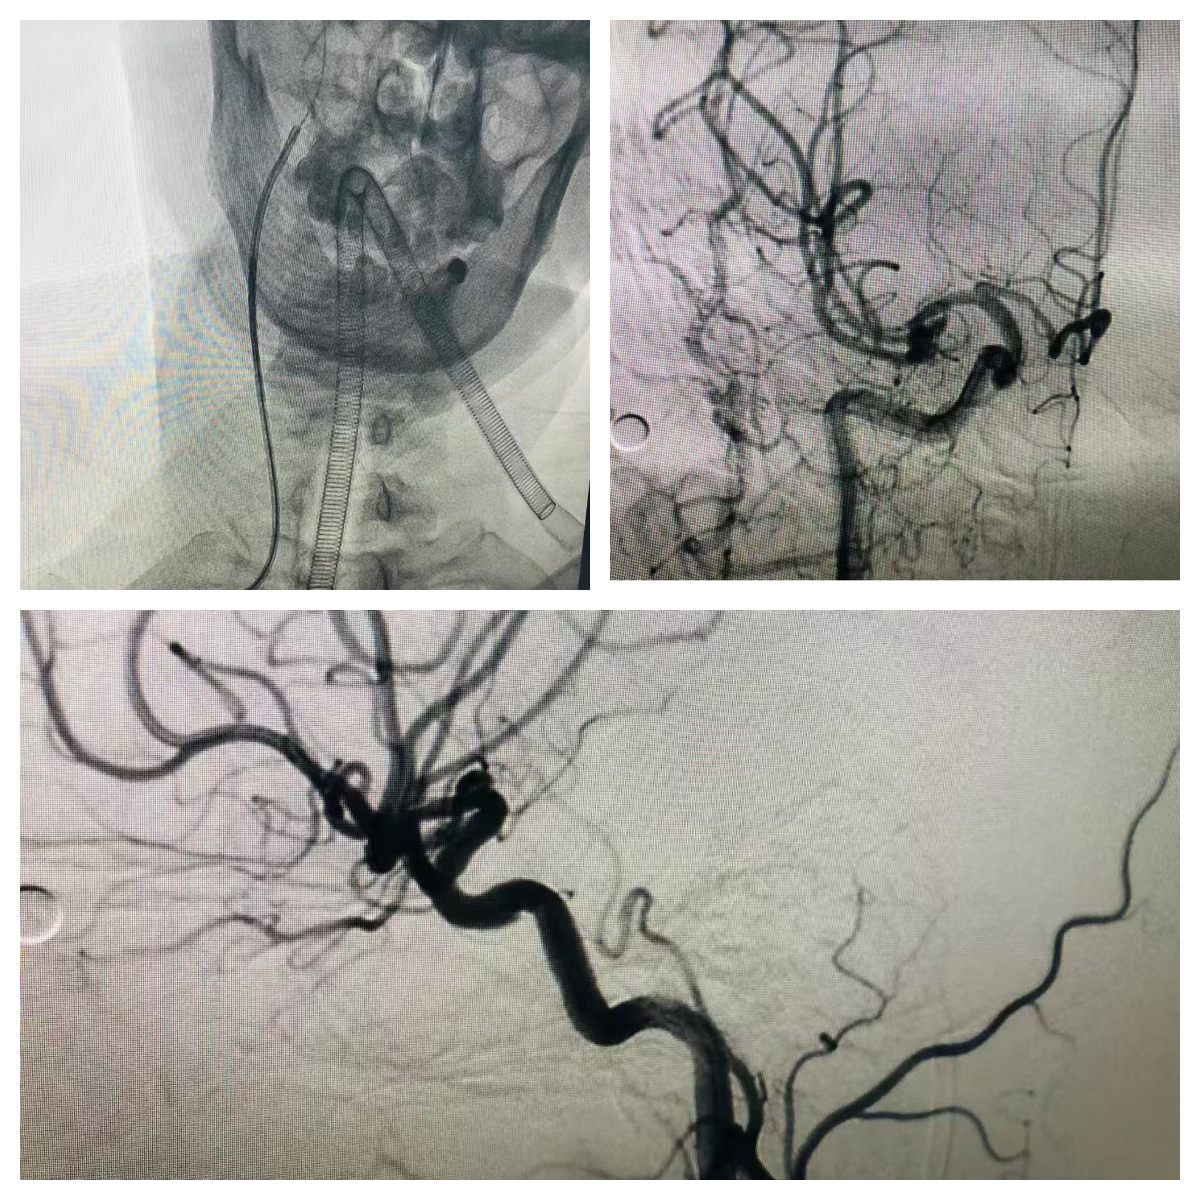

技术的精准实施离不开强大的硬件支撑与团队保障。我院已配备先进的数字减影血管造影(DSA)系统,其高清晰度成像功能可实时显示颅内颈内动脉、椎动脉、大脑前动脉、大脑中动脉等各级血管的解剖结构,精准捕捉血管狭窄、畸形、动脉瘤等病变细节,为诊断提供“火眼金睛”般的影像支持。同时,科室配备了全套专用介入器械,包括桡动脉穿刺针、造影导管、导丝及术后压迫止血装置等,确保每一步操作规范精准。

微创精准诊疗新突破——我院神经内科开展经桡动脉行脑血管介入术

此次我院引进的经桡动脉行脑血管介入术,实现了脑血管介入诊疗的“微创革命”。该技术通过手腕部的桡动脉穿刺建立介入通道,仅需2-3毫米的微小创口即可完成经桡动脉行脑血管介入手术。桡动脉位置表浅、易于压迫,且周围无重要神经和血管毗邻,从根源上降低了血管损伤风险。更重要的是,术后无需长时间卧床,患者穿刺完成后即可下床活动,当天就能正常进食、行走,大幅提升了就医舒适度,也减少了家属的陪护压力。